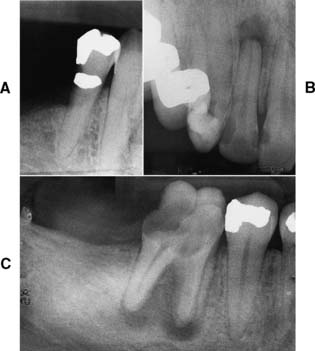

Patients who have definite symptoms seldom present problems in diagnosis, because pain is generally their chief complaint. When there is doubt concerning pulpal health, however, patients should be examined radiographically during the mouth preparation phase, and the films should be carefully inspected for signs of periapical disease (a radiolucency or widening of the periodontal ligament space). When there is doubt regarding the endodontic prognosis of a tooth, radiographic findings (Fig. 6-12) should always be evaluated in reference to the results of percussion and vitality tests.

As a general rule, conventional (or orthograde) rather than surgical (or retrograde) endodontics should be performed if possible—not only because additional trauma results from the surgical approach but also because apicoectomy adversely affects the crown/root ratio and thus the support of the planned prosthesis. If an existing post prevents access to a recurrent periapical lesion, the post can usually be removed. (A Masserann kit has shown some success with this; see Chapter 12.) When a post and core restoration is needed in an endodontically treated tooth, 3 to 5 mm of apical seal should be retained (see Chapter 12).